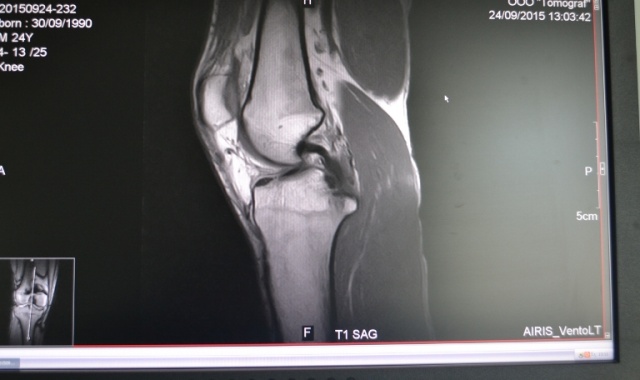

Магнитно-резонансная томография (МРТ) - один из самых информативных и безопасных современных методов диагностики.

Безусловно, МРТ дает более широкий анализ и полную «картинку» по сравнению с компьютерной томографией, не говоря уже о простом УЗИ или рентгенографии. На сегодняшний день МРТ - это самый полный и точный метод диагностики.

Высокое качество снимков удовлетворяет специалистов всех профилей.